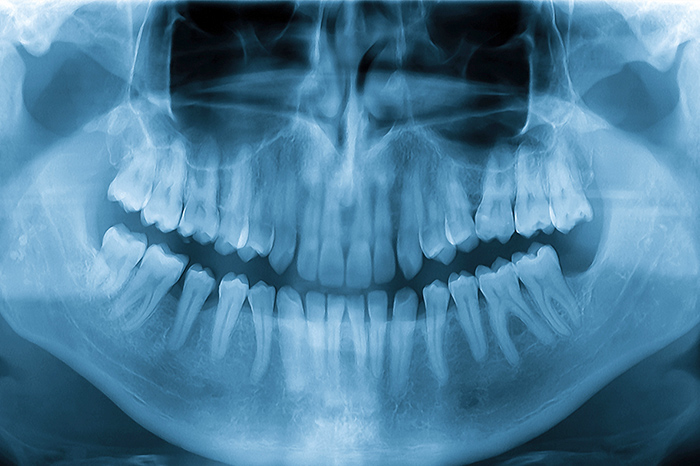

歯科用CT

肉眼では確認できない根管内部の状態を把握するために用いる精密検査機器です。むし歯の進行度や組織へのダメージを正確に確認できます。

歯や神経、血管のなどの位置を立体的に把握できる精密検査機器です。親知らずの抜歯やインプラントの手術など、さまざまな治療で用いられます。